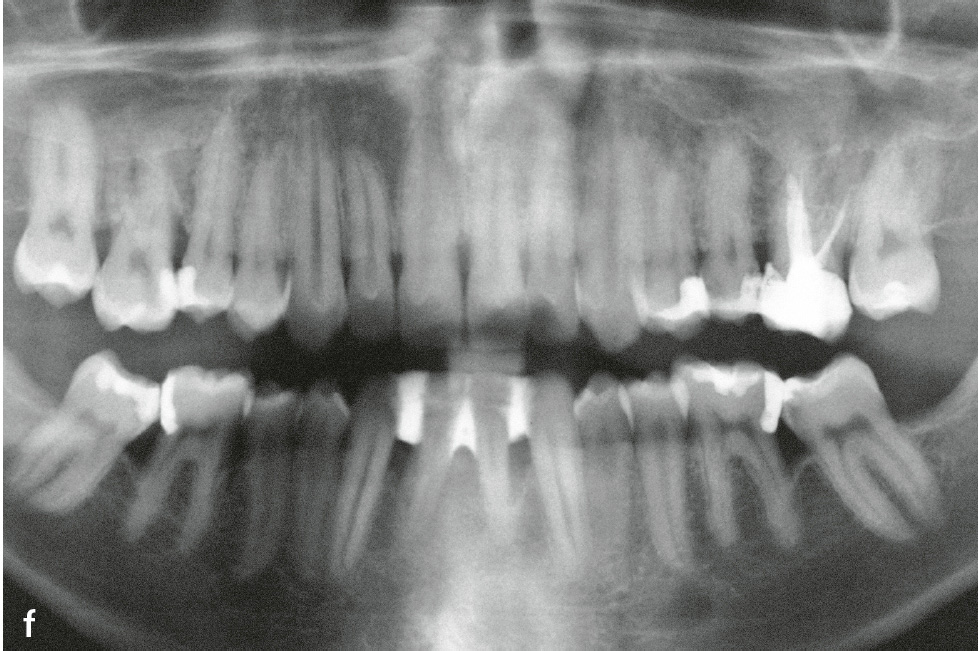

Die Therapie der Hautveränderungen erfolgt zum Teil mit oralen Retinoiden, aber auch urathaltigen Salben. Eine erfolgreiche Therapie der Parodontitis ist möglich. Der Erfolg scheint von verschiedenen Faktoren abzuhängen: möglichst frühzeitiger Beginn (ggf. schon im Milchgebiss), Elimination von A. actinomycetemcomitans und engmaschige professionelle Nachsorge (Abb. 1e und f)7.

Abb.1e und f e) Klinische Ansicht im Alter von 22 Jahren; 14 Jahre nach nichtchirurgischer antiinfektiöser Therapie mit unterstützender Gabe von Amoxicillin und Metronidazol und anschließender unterstützender Parodontitistherapie anfänglich alle 2, später alle 3 Monate; f) Panoramaschichtaufnahme zu Abb. 1e.